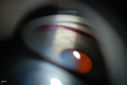

Gonioscopy, Blood in the Anterior Chamber from Hyphema629 viewsPatient comes in with blunt trauma to the right eye due to a BB gun incident. Patient was present with a hyphema at 8-o'clock about 1mm thick. Gonioscopy photos were then taken to show blood from the hyphema entered into the anterior chamber. Patient had no angle recession in the right eye.      (0 votes)